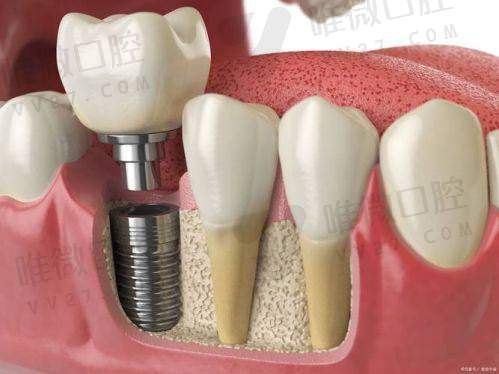

种植牙2980元起,这价格靠谱吗?

乍一听种植牙只要2980元是不是有些惊讶?其实这也是基础种植体品牌——韩国登腾类的价格含义,而且是含种植体+基台+牙冠的“全包价”,没有那些“临时牙、结构费另算”的猫腻。当然,如果你注重美国品牌、德国品牌,也能选,比如3680起的皓圣、8800元起的ITI,明确标注。真正做到了“口袋有多深,牙就种多大”这种按需选择。